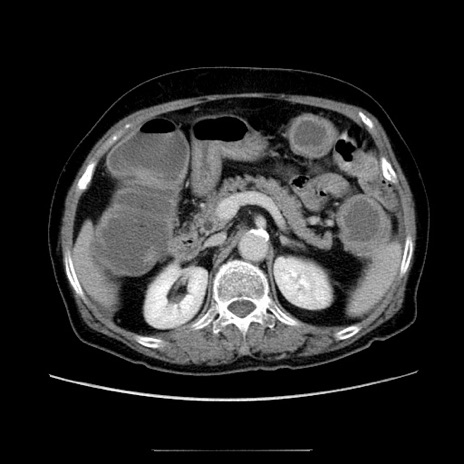

冠状断像

【症例】70歳代女性

【主訴】お腹が張る

【現病歴】1週間くらい前から腹部膨満の自覚あり。昨日夜から増悪したため、本日救急外来受診。

【身体所見】意識清明、BT 36.5℃、BP 165/106mmHg、HR 80bpm、SpO2 98%、腹部:膨満、軟、自発痛・圧痛なし、触診にて不快感あり、腸蠕動音:減弱

【データ】WBC 12600、CRP 1.04